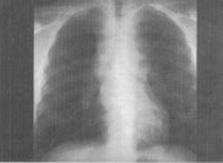

患者男,21岁,1个月前触及颈部淋巴结肿大,现有上腔静脉综合征,结合胸片,最可能的诊断()。

A、结节病

B、淋巴结核

C、转移性淋巴结肿大

D、淋巴瘤

E、胸腺瘤

D